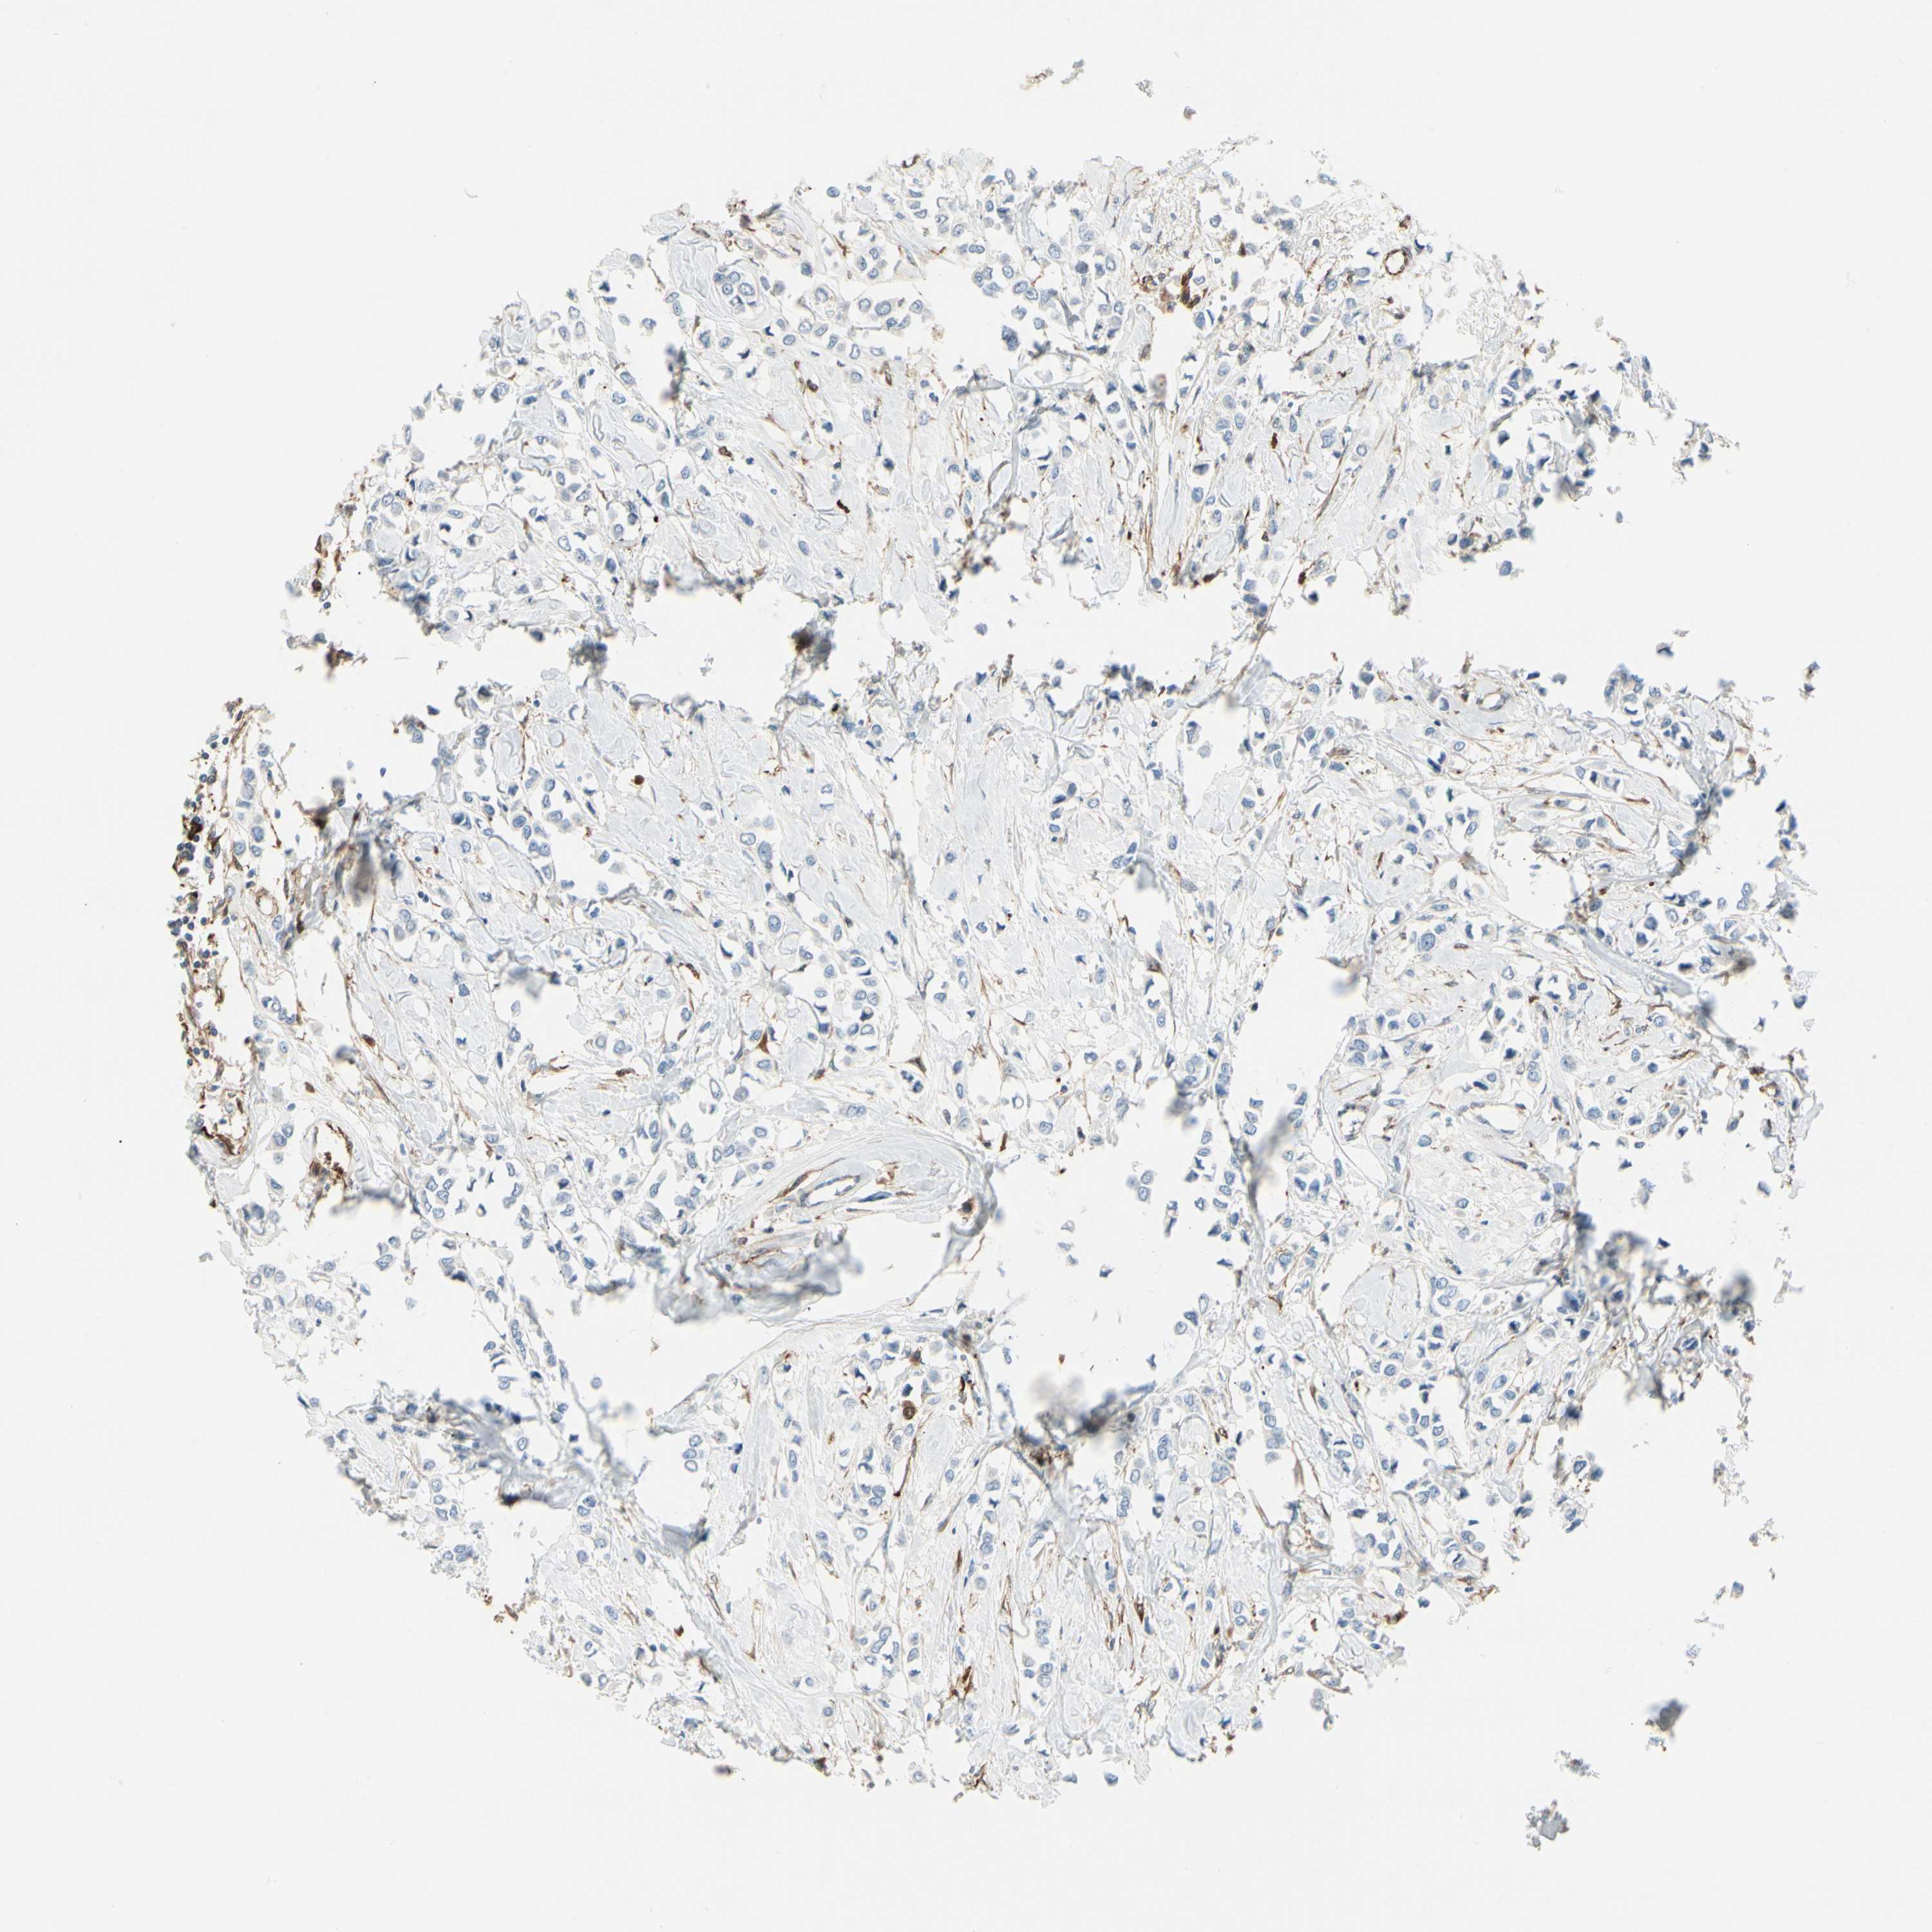

BRCA TCGA BRCA VALIDATION PROTEIN EXPRESSION